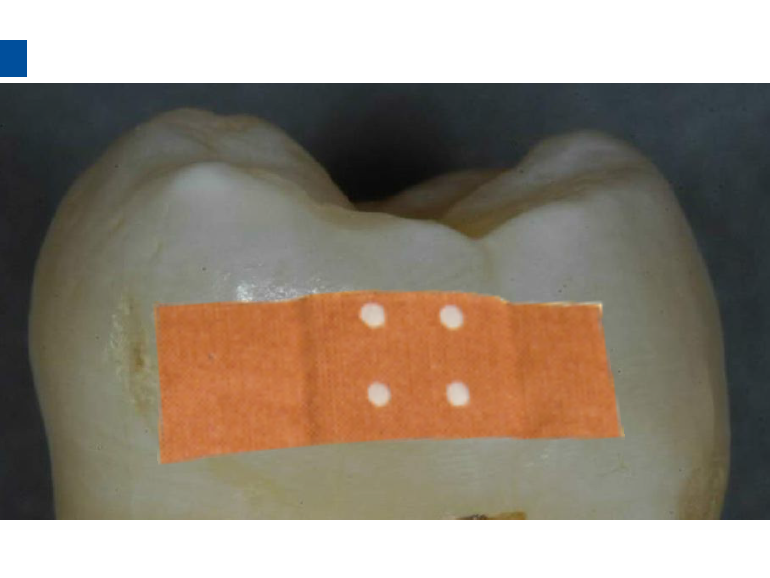

1、治疗之前清洁患牙及邻牙,冲洗干净,上橡皮障。避免使用如Flexi Dam之类的热塑性橡胶材质的橡皮障。放置合适的楔子进入牙间隙,将楔子柄部弯曲或折断可以让楔子更好的进入邻面。楔子必须进到牙间隙足够的深度才能保证分开患牙与邻牙,在整个治疗过程之中都要保证楔子的存在,两牙之间分开约50μm就可以顺利完成治疗。

2、将配套邻面治疗的注射头旋紧在爱康酸蚀剂Icon-Etch的注射器头部,然后将注射头薄膜置于牙间隙,注意要把注射头薄膜的绿色面与需要治疗的牙面紧贴,因为材料只会从绿色面溢出。

3、旋转注射器柄部1-2圈,使在龋损牙面上有足量的爱康酸蚀剂Icon-Etch,静置两分钟并除去多余材料